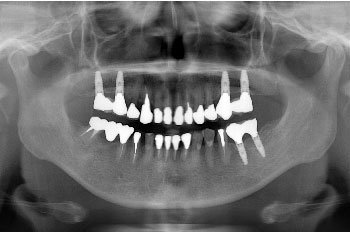

Before

今回行った治療は、奥歯がなかったのが一番問題でしたので、奥歯のインプラント、被せ物が古くなり虫歯や歯周病が進んでしまっていたので古くなった被せ物のやりかえを中心に行いました。その際、全体的な咬み合わせのズレや不調和も見られたので、バランスを見ながら治療を進めていきました。

| 治療の内容 | インプラント治療6本と骨造成、被せ物の入れ替えでセラミック補綴を8本替える治療。 |

| 期間・回数 | 1年4ヶ月・12回(カウンセリング・検査・歯周病治療を含む) |

| 費用 | 自由診療:スタンダードインプラント✕6歯+骨造成+セラミック補綴✕8歯 合計 2,350,000円(税込2,585,000円) |